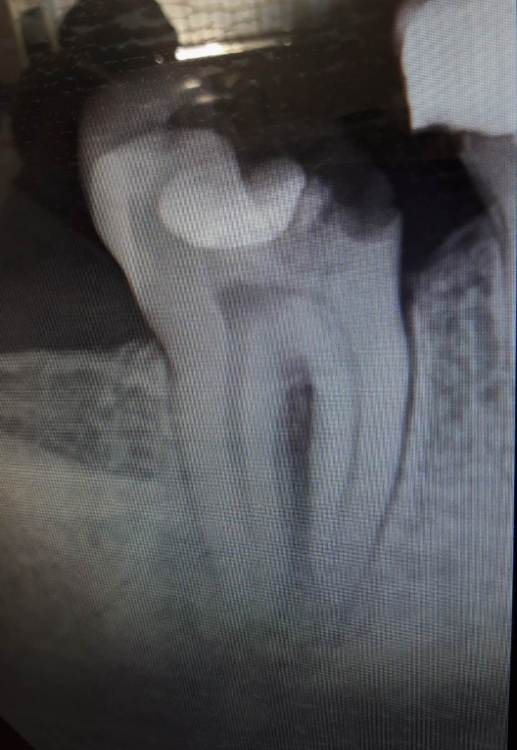

Gammy Опубликовано 28 июля, 2021 Поделиться Опубликовано 28 июля, 2021 (изменено) Здравствуйте. За качество снимков сразу извиняюсь, в клинике куда ходила, только сфотографировать с экрана дали. Нижняя 7ка, старая большая пломба, откололся кусок зуба, пока не болит. На консультации сначала сказали выбирать: 1. коронка, но не ясно как выйдет, ещё надо пытаться лечить (вроде как нерв умер и идет воспаление). 2. удалять и имплант. А потом стали склонять к импланту, надежнее и результат более предсказуем. Вот я и озадачилась Есть смысл с таким зубом бороться за коронку? И 6ка, тоже разваливается, нервы удалены давно. По снимку реально сказать, можно ли коронку делать или удалять и имплант? Изменено 28 июля, 2021 пользователем Gammy Ссылка на комментарий

chervoncevdaniil Опубликовано 29 июля, 2021 Поделиться Опубликовано 29 июля, 2021 Я бы оба пробовал перелечить,по 7 лучше сделать КТ 2 1 Ссылка на комментарий